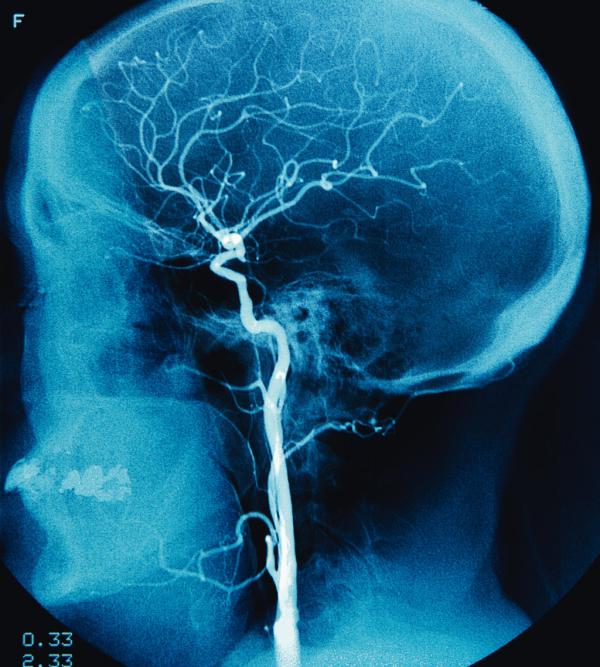

Krew daje napęd. Ale może też wyrządzić krzywdę. Jej ofiarami padają jedne z najważniejszych komórek naszego ciała – neurony. Następuje udar.